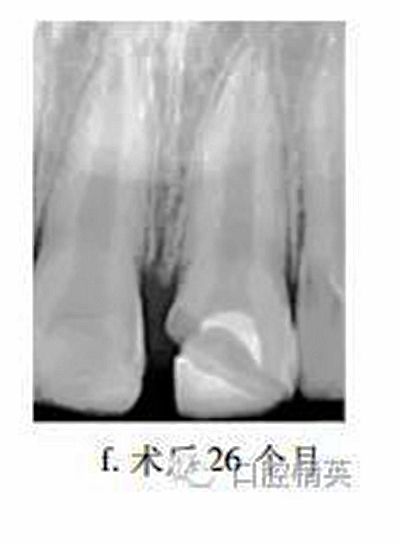

26個(gè)月后復(fù)查,患牙無(wú)不適,牙髓活力測(cè)試較正常牙齒略低,冠部充填物部分脫落,X線片示:患牙蓋髓劑下方可見連續(xù)薄層高密度影像,髓腔縮窄,根尖孔聚攏,牙根長(zhǎng)度較鄰牙無(wú)明顯差異(圖f)?;佳廊コ糠植Aщx子水門汀,備釘?shù)溃魸瘢{米樹脂修復(fù)冠缺損,調(diào)牙合拋光。

眾多臨床研究表明,MTA用于活髓切斷術(shù)的臨床療效優(yōu)于傳統(tǒng)的蓋髓劑氫氧化鈣,除去MTA較氫氧化鈣具有更好的封閉性以外,低細(xì)胞毒性是其另一重要特點(diǎn)。MTA體外實(shí)驗(yàn)中可促進(jìn)正常牙髓細(xì)胞的牙向分化能力,亦能提高成骨細(xì)胞的體外骨向分化能力。有學(xué)者發(fā)現(xiàn)早期炎癥狀態(tài)下,牙髓干細(xì)胞的體外增殖與成牙能力降低,而成骨能力上調(diào),本病例26個(gè)月復(fù)查X線片中發(fā)現(xiàn)MTA下方有薄層連續(xù)高密度影像,牙根伸長(zhǎng),根尖孔聚攏,提示創(chuàng)傷暴露后的牙髓(干)細(xì)胞在MTA誘導(dǎo)下,具有較強(qiáng)的修復(fù)能力。